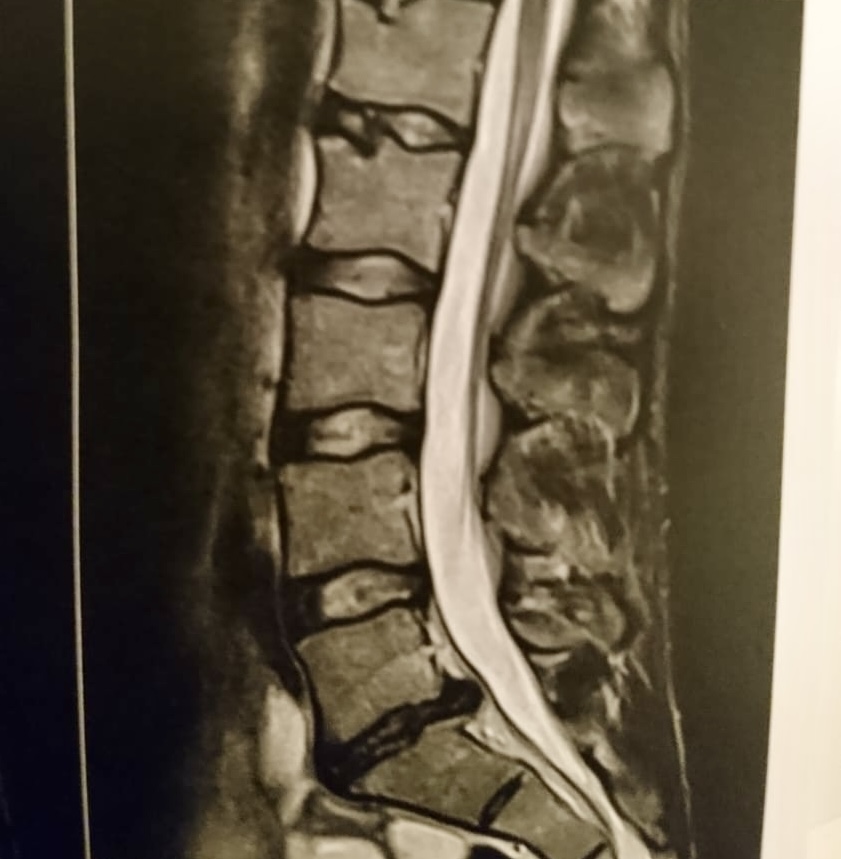

Viele unserer Patienten haben diese Beschwerden schon seit Wochen oder sogar Monaten – oft trotz Physiotherapie, Spritzen oder Schmerzmitteln. Häufig zeigt auch ein MRT einen Bandscheibenvorfall oder eine Einengung der Nervenwurzeln (z. B. durch Arthrose oder Vorwölbungen).

Gründliche Untersuchung, Sichtung der MRT-Bilder, klare Diagnose und Empfehlung.